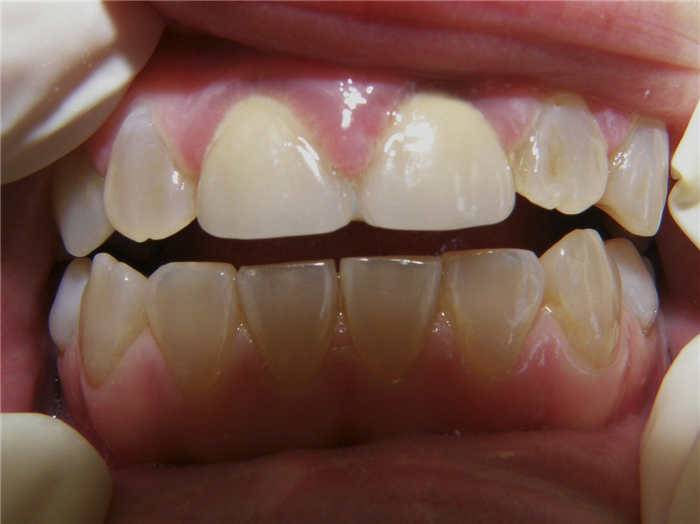

Общие сведения из анамнеза двух сестер: молочные зубы были серые, полупрозрачные и очень хрупкие. Наблюдалась задержка физиологической резорбции корней, поэтому молочные зубы удалялись. Кариесом временные зубы не поражались и никогда не болели. Постоянные зубы прорезались в нормальные сроки, но сразу же имели серый цвет и прозрачность (рис. 1а).

Рис. 1а. Зубы младшей сестры.

Дефекты коронок многократно пломбировались, но безуспешно. Пломбы выпадали быстро, иногда через несколько часов. У младшей сестры в 15—16-летнем возрасте были удалены четыре зуба из-за полного их разрушения. При клиническом исследовании установлено, что симптомы заболевания у сестер аналогичны, однако более выраженны у младшей сестры. Зубы имеют необычный цвет, но окраска зубов неоднородная. Цвет колеблется от серого до светло-коричневого с янтарной полупрозрачностью. У младшей сестры зубы окрашены более интенсивно, и здоровый вид у нее имеют только восьмые зубы. У старшей сестры нормальный цвет имеют верхние премоляры, а также сохранившиеся моляры (рис. 1б).

Рис. 1б. Зубы старшей сестры.

У обеих сестер более интенсивно окрашены зубы нижней челюсти. У старшей сестры зубы более крупные и имеют бочкообразную форму, у младшей бочкообразность зубов менее выраженна. Все зубы устойчивы. Имеются множественные сколы зубов. Края сколов находятся под десной, а линии сколов проходят по предполагаемым границам полостей зубов. Полости зубов облитерированы. Все участки обнаженного дентина имеют коричневый цвет, тверды и безболезненны при зондировании (рис. 3).